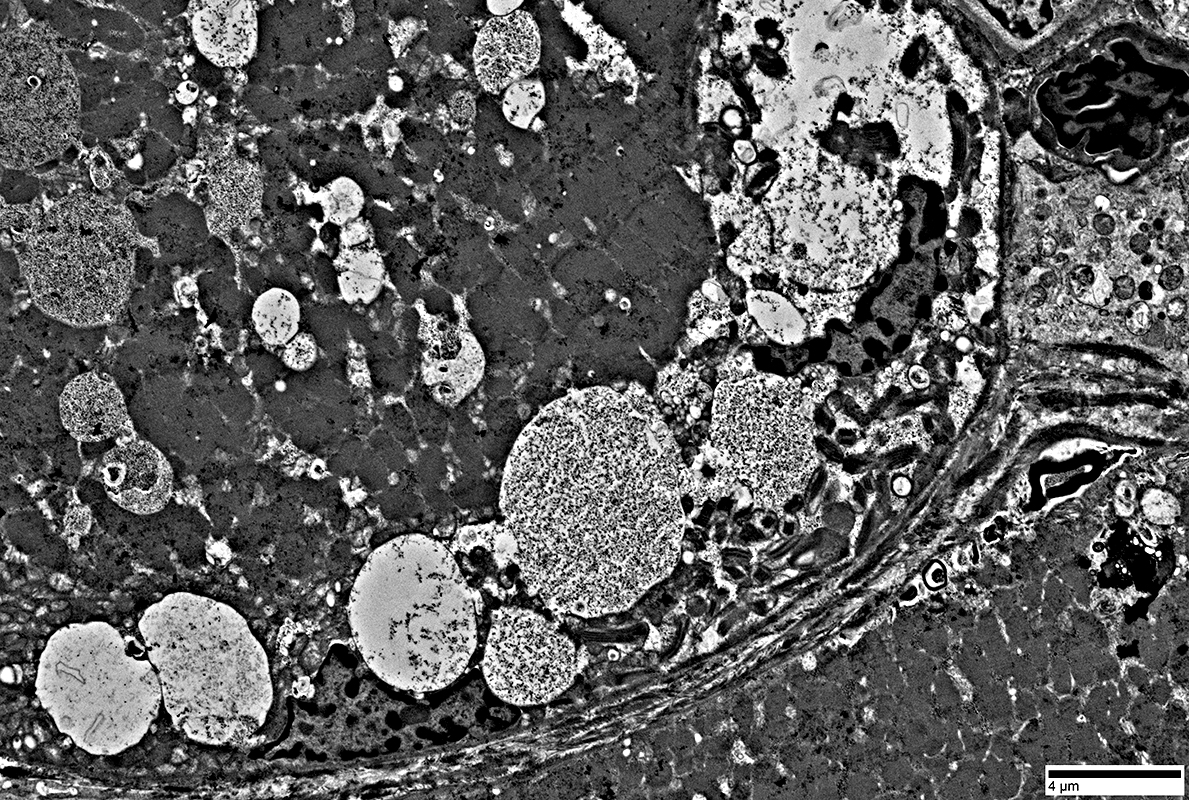

Inclusions & Vacuoles: Different Types in muscle fibers in IM-VAMP

- Filamentous (Black arrow; Above)

- Osmophilic (Red arrow; Above): Possible remanants of nuclear membranes

- Autophagic

- Membrane-like (White arrow; Above): Multilayered; Irregular shapes; May be within larger, "vacuolar", structures

- Tubulovesicular material (Below)

From: R Schmidt

Aggregates contain

Filaments

A few myeloid structures & mitochondria

|